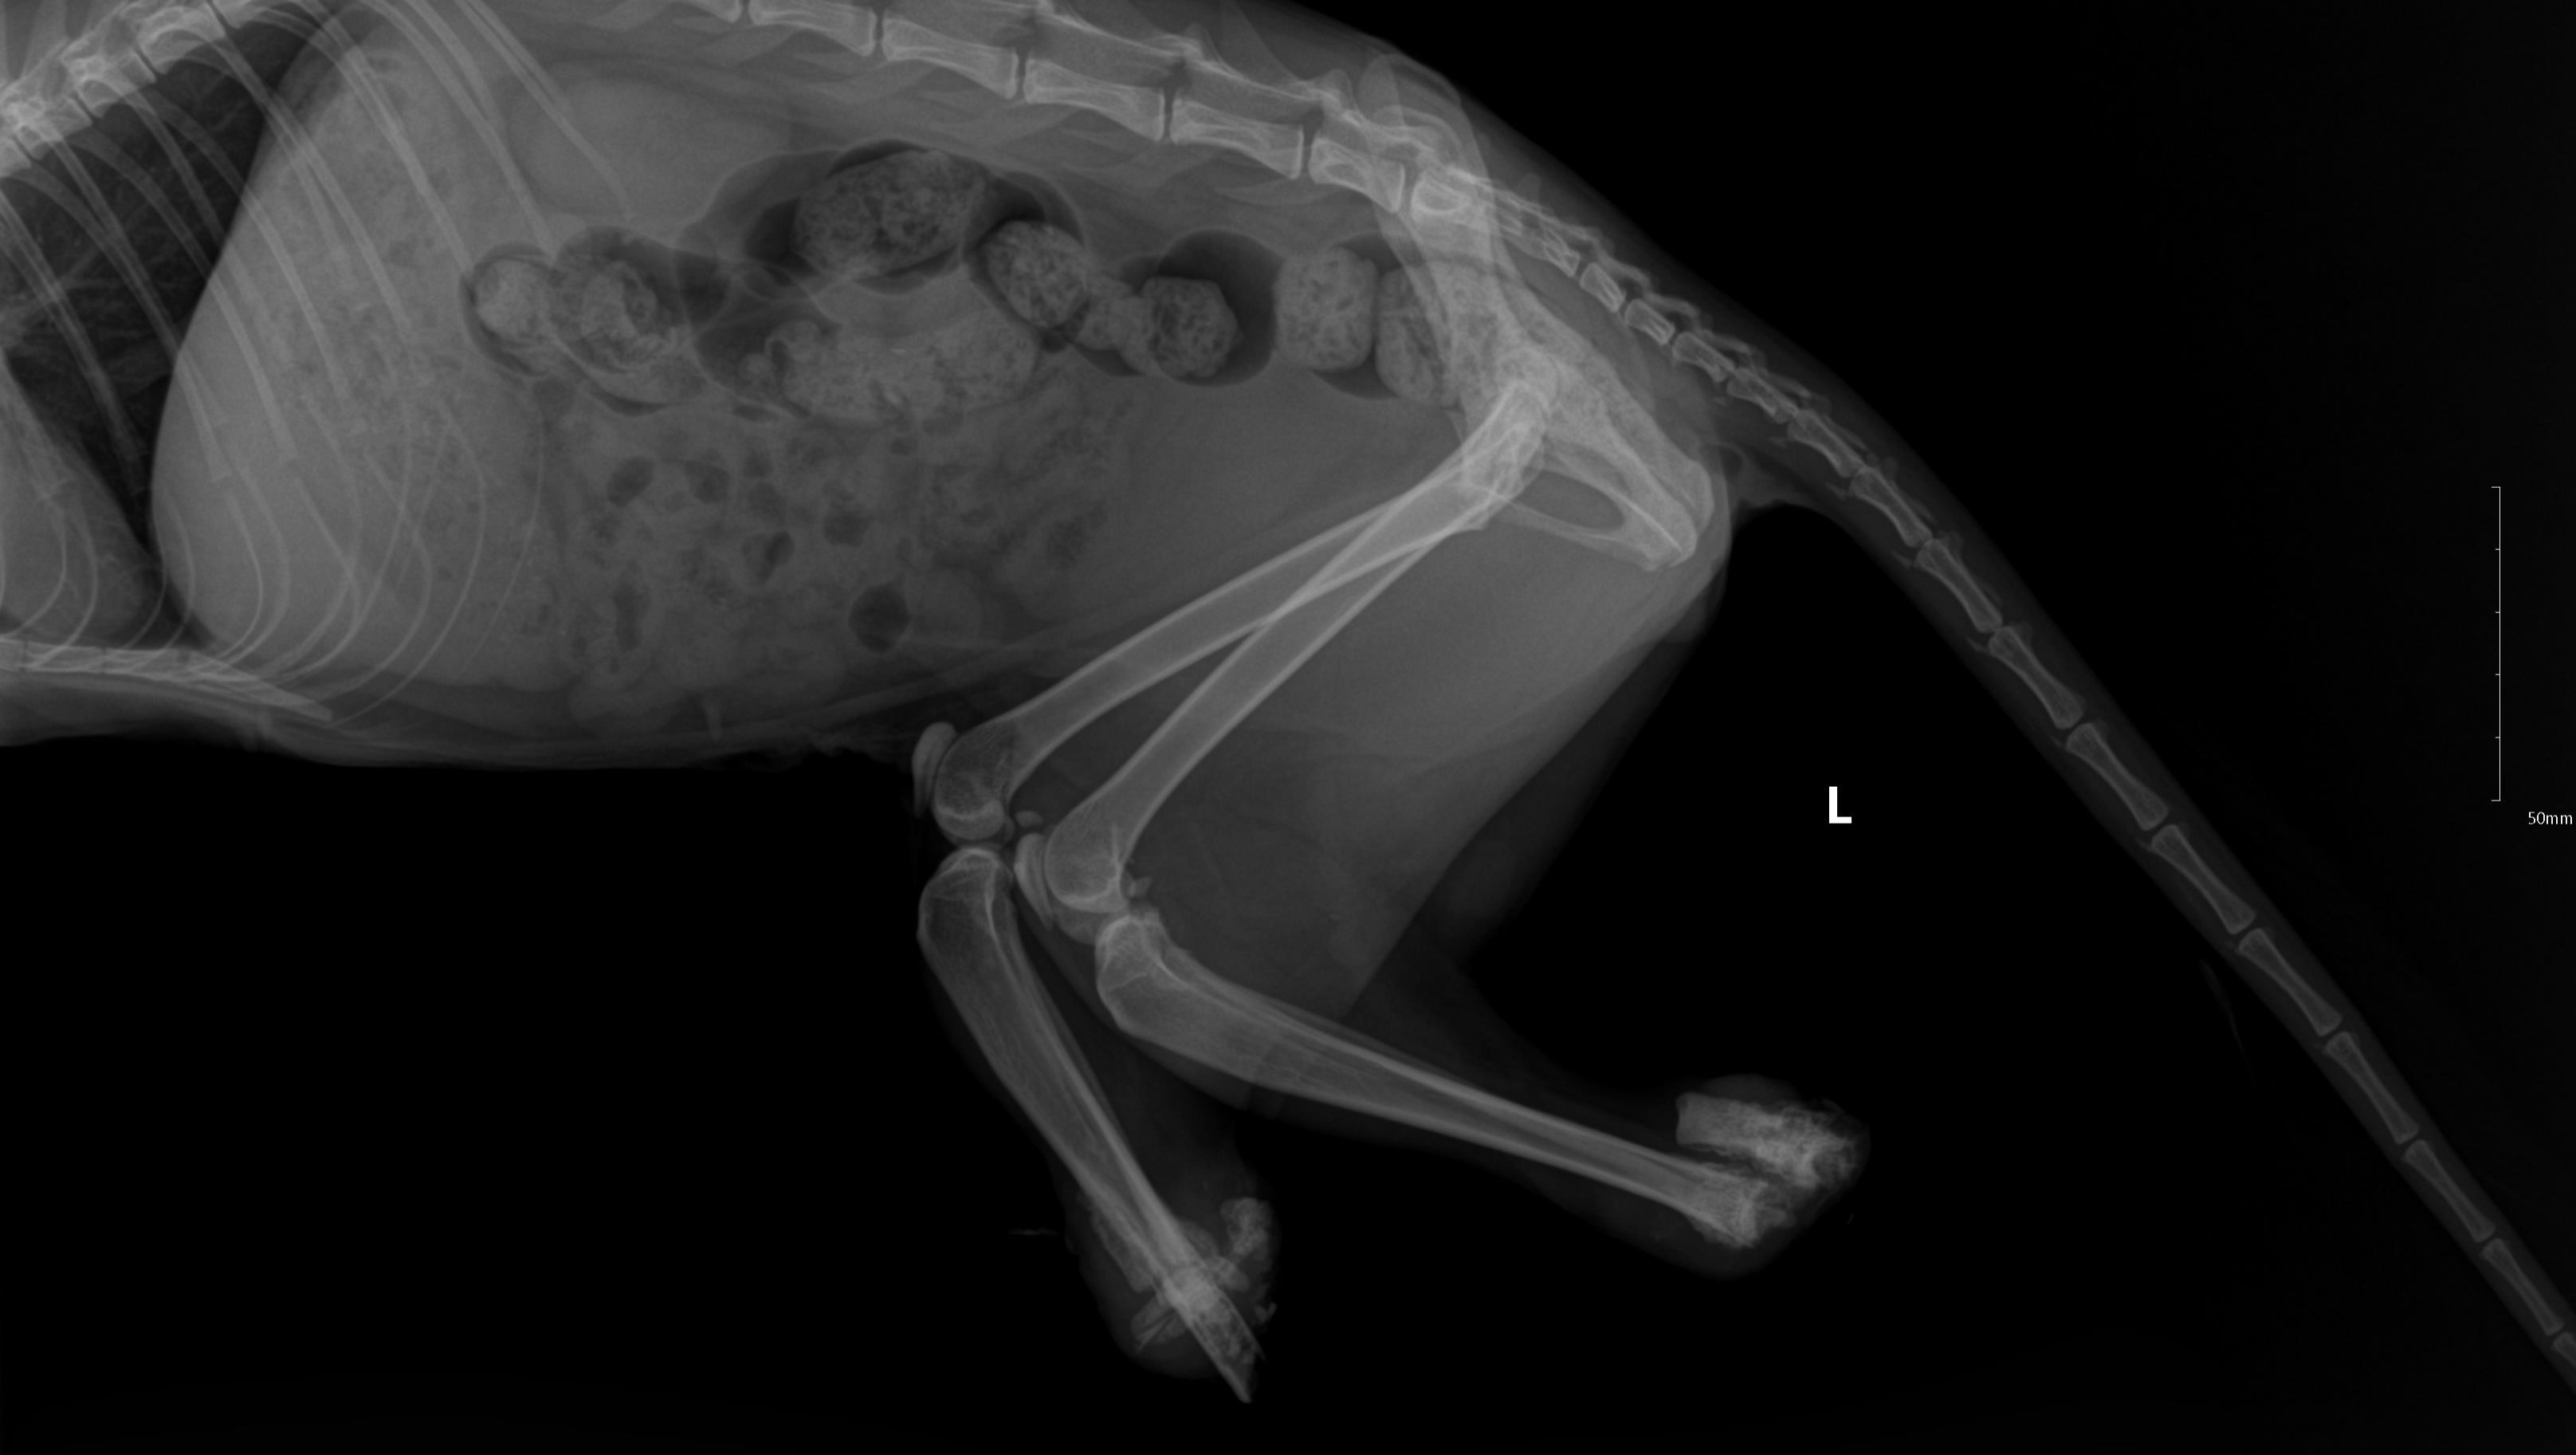

One day someone or someone’s decided to cut both of Maggie's back legs off below her knees. We know that is hard to hear and her veterinarian team and caretakers have been shedding tears about this senseless, horrible and disgusting act. Are we angry, of course, but right now Maggie is the focus of our attention. She doesn't deserve more anger or fear.

Michele drove straight to the shelter and brought her home. She reached out to our hero veterinarian team and they got Maggie in the next day. There was no way to save what was left of her bottom legs (they cut them off above her feet), so she had no choice but to amputate them to the knees and Maggie spayed at the same time.

We know questions will be asked about is this what really happened? Yes, it is as there were witnesses seeing the act happen. Will the perpetrator(s) be punished, unlikely, as usual as no one is coming forward with who did this to her. Also, when looking at her x-rays you can see her bones were cut right through.

We know these images are hard to see and we cannot imagine the trauma and pain she must have been in. These were taken when she arrived at the shelter before her surgery.